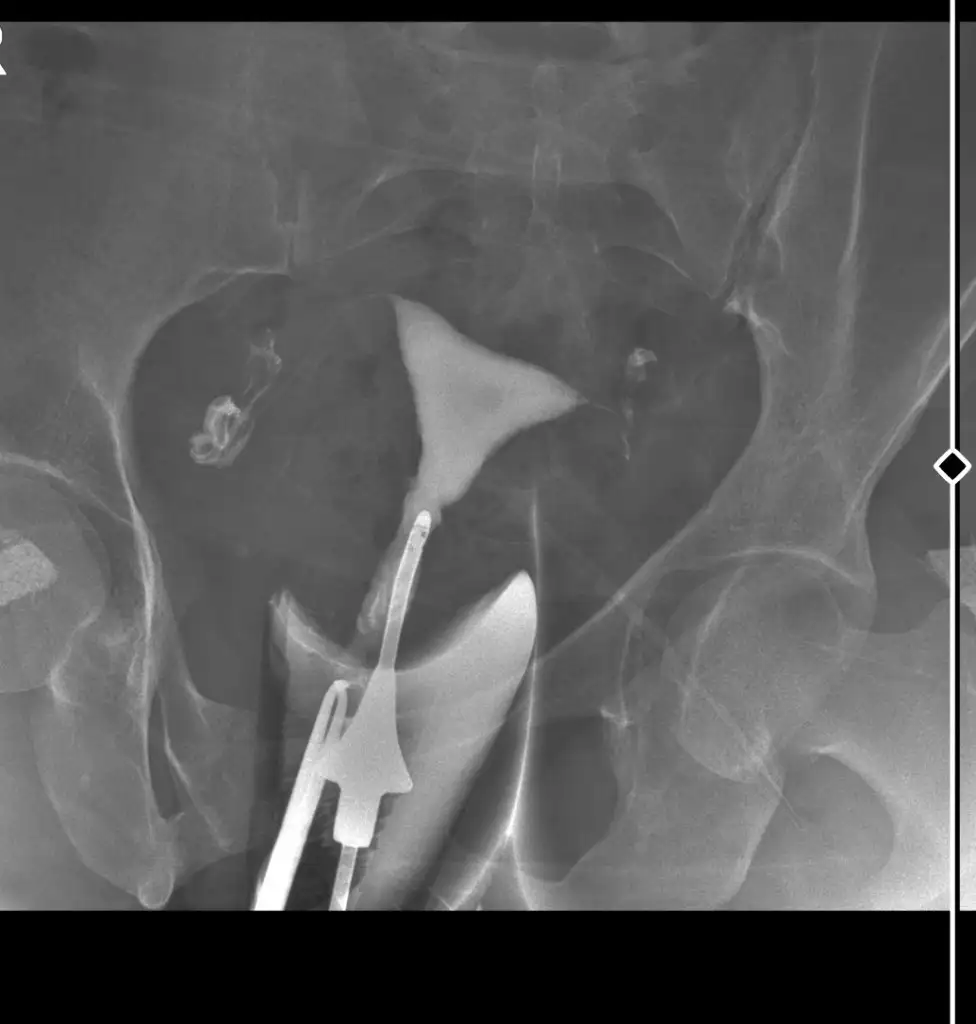

Merhaba uzun zaman olmuş ama inşallah girerde görürsünüz bende rahim filmi çektirdim ama baya zor oldu açılmadı doktor çok ugrasti Sivi hep geri geldi açılmadı dedi doktor ama sonradan açıldı dedi sizce acilmis mi anlayan varmı

• Screenshot_2024-03-29-02-33-31-69_40deb401b9ffe8e1df2f1cc5ba480b12~2.webp